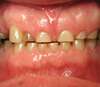

• Des dents usées, plus courtes, avec des bords cassés ou ébréchés

dents usées et mâchoires douloureuses

dents abîmées par le bruxisme

Quelles sont les conséquences du bruxisme ?

Sans prise en charge, le bruxisme peut entraîner :

• Des usures dentaires importantes nécessitant des restaurations complexes

• Des fissures ou fractures de dents